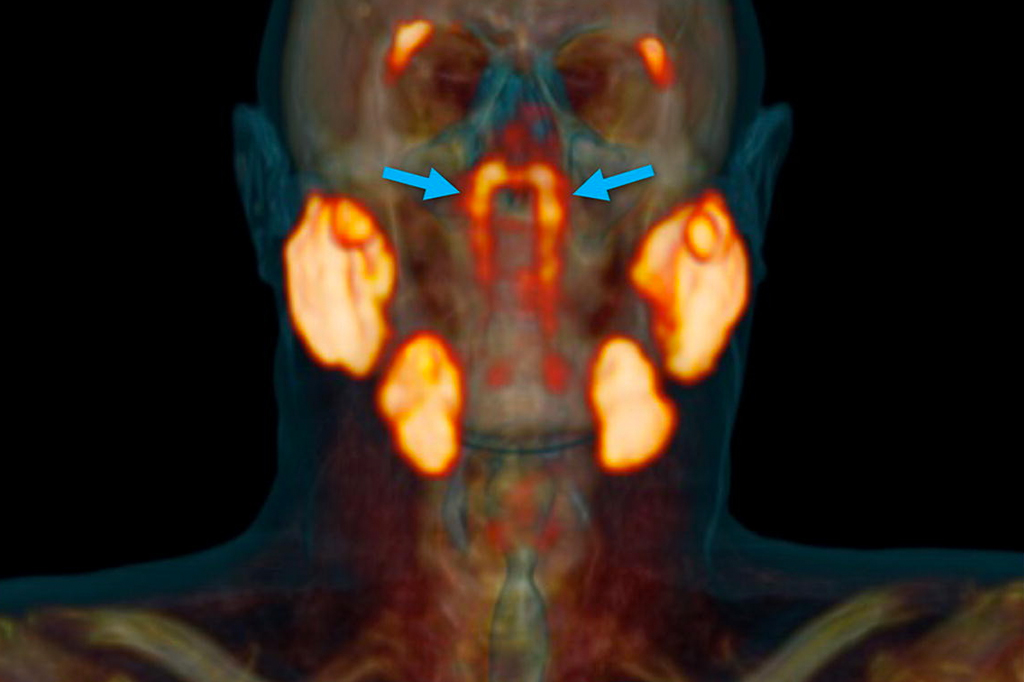

Pesquisadores podem ter encontrado duas novas glândulas no crânio humano